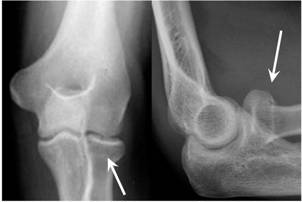

• You have a very small break in the head or neck of the radius bone at your elbow.